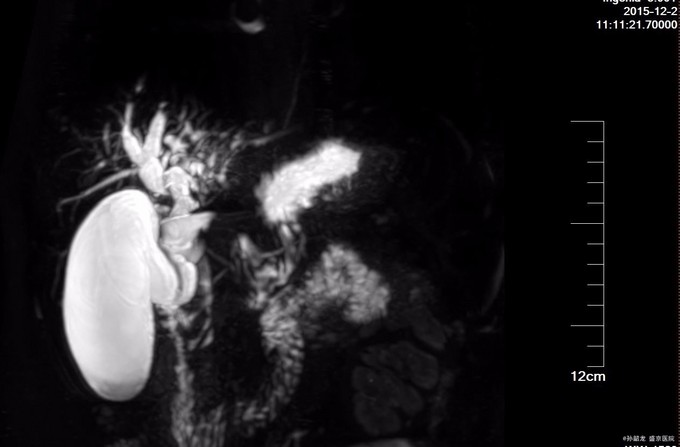

查体:全身皮肤及巩膜无黄染,腹软不胀,未见胃肠型及蠕动波,全腹平软,全腹无压痛及无反跳痛,无肌紧张,Murphy's征(-),肝区叩痛(-),双肾区叩击痛(-),移动性浊音(-),肠鸣音6次/分。 辅查: 肝功能化验,总胆红素及直接胆红素正常,转氨酶有升高。 MRCP提示胆囊增大,肝内外胆道内多发结石,伴胆道梗阻。 腹部BUS提示 1.肝外胆道梗阻, 2.肝门部胆管至胆总管内结石, 3.肝内胆管结石。